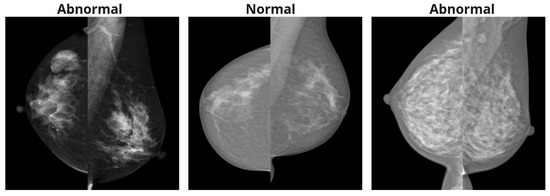

There are a total of six datasets utilized in this study. The summary of the datasets is provided in Table 1. Additionally, example images are provided in Figure 1.

Figure 1. Example craniocaudal (CC) and mediolateral oblique (MLO) view pairs of one normal breast and one breast with an abnormality, taken from various mammography datasets. In each pair, the CC view is shown on the left and the MLO view on the right.